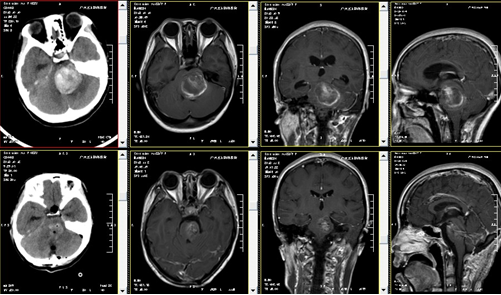

门诊以诊断:1.脑干出血(血管畸形?);2.梗阻性脑积水收入院。入院后予完善相关检查,头颅MRI示:1.脑干血肿形成(出血量约为30ml),待排血管畸形;2.幕上梗阻性脑积水;3.MRV:左侧横窦及直窦未见显示,上矢状窦中前段信号欠均匀;4.DTT(白质纤维束三维重建)检查:病变内未见纤维束,周围纤维束受推压,左侧皮质脊髓束病变以下节段未见显示。目前诊断明确,有手术指征,完善术前准备后,由林涛主任主刀行“脑干血管畸形切除术+血肿清除术”,手术顺利。术后复查头颅CT、MRI呈术后改变。术后病理结果回报:符合动静脉畸形并血肿形成。术后约半个月治疗,张小姐可短距离自行行走。病情好转出院。

以下影像资料,上排为术前,下排为术后。